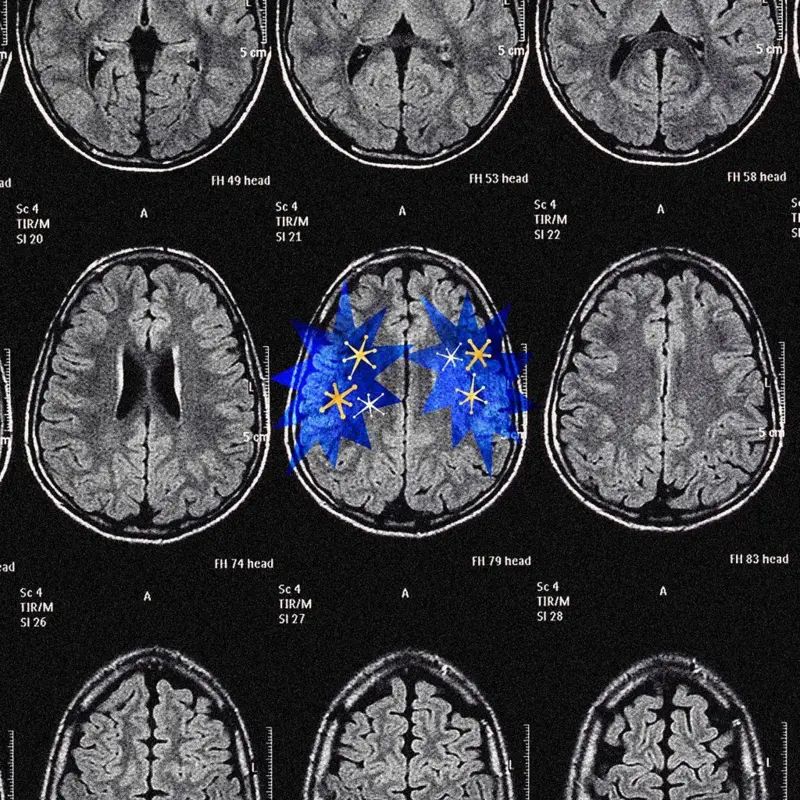

Para entender por qué, necesitamos analizar cómo dos partes de nuestro cerebro —la corteza cerebral y el sistema de recompensa, incluida la dopamina— nos impulsan en diferentes direcciones.

El cerebro sin dopamina

La corteza cerebral es la máquina universal de comprensión de nuestro cerebro.

Hoy sabemos que esta afección afectaba específicamente a la región cerebral llamada sustancia negra, uno de los pocos lugares del cerebro que produce dopamina.

Básicamente, la encefalitis letárgica muestra lo que sucede cuando el cerebro se queda sin dopamina: se paraliza.

Y no solo eso. Lo sume en un estado de inacción y falta de experiencia en el que no siente la necesidad de hacer absolutamente nada.

Todo lo que hacemos, más allá de los reflejos básicos, como masticar la comida cuando la tenemos en la boca, está motivado por la dopamina.